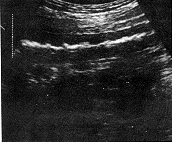

按照小肠肿瘤的超声图像分型〔7〕,本组21例转移性小肠肿瘤中19例均属壁厚型。肿瘤大体形态和长、短轴切面为受累肠壁增厚分别显示为假肾和靶环征(图1.2)。厚度范围0.8~2.0cm,长度范围3.0~7.0cm;2例长度>10cm分别为鼻咽部恶性淋巴瘤和白血病远端小肠侵犯,沿肠壁长轴浸润呈均匀低回声区(图3)。2例属腔外肿块型。11例为卵巢癌腹膜种植性转移连同小肠襻与壁层腹膜之间Φ3.0cm中等强回声型肿块并有多量腹水(图4)。另1例为睾丸精原细胞瘤小肠转移,相当于远端小肠与膀胱之间见Φ6.0cm中等回声实性肿块伴边缘肠腔强回声及膀胱内游离气体,提示:小肠外生型肿瘤侵犯膀胱并有内瘘形成,X线气钡双重对比造影后患者排出白色钡剂尿液(图5,6)。

沿肠壁长轴广泛浸润 卵巢癌侵犯邻近小肠

图3 白血病小肠侵犯 图4 腔外肿块型转移性小肠肿瘤